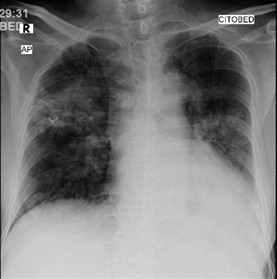

Pulmonary tuberculosis remains a global health issue, with one of the challenges being the adverse side effects of anti-tuberculosis drugs that can interfere with the success of therapy. This case reports a 67-year-old man with pulmonary tuberculosis who experienced a rifampicin-induced drug eruption and pyrazinamide-induced hepatitis during first-line antituberculosis combination therapy. After temporarily discontinuing the antituberculosis regimen, the patient was given supportive therapy with corticosteroid and antihistamine for the drug eruption, and stronger neo-minophagen C injections for the hepatitis. After stabilization, the regimen was adjusted to a combination of isoniazid and ethambutol, and streptomycin was added as the third agent; however, due to an allergic reaction, streptomycin was replaced with levofloxacin. The new regimen, isoniazid-ethambutol-levofloxacin, combined with appropriate management of the adverse reactions resulted in favorable clinical outcomes, marked by the disappearance of the itchy red rash on the face and body, improvement in liver function as seen from liver enzymes and bilirubin levels, and a stable general condition. This case report emphasizes the importance of being aware of the adverse side effects of antituberculosis regimens, especially in elderly patients. Regular monitoring of liver function, early detection of drug reactions, and safe and individualized regimen adjustments are important strategies to prevent complications without compromising the success of tuberculosis treatment. This case provides important lessons regarding a cautious, evidence-based clinical approach to addressing serious side effects of antituberculosis drugs.